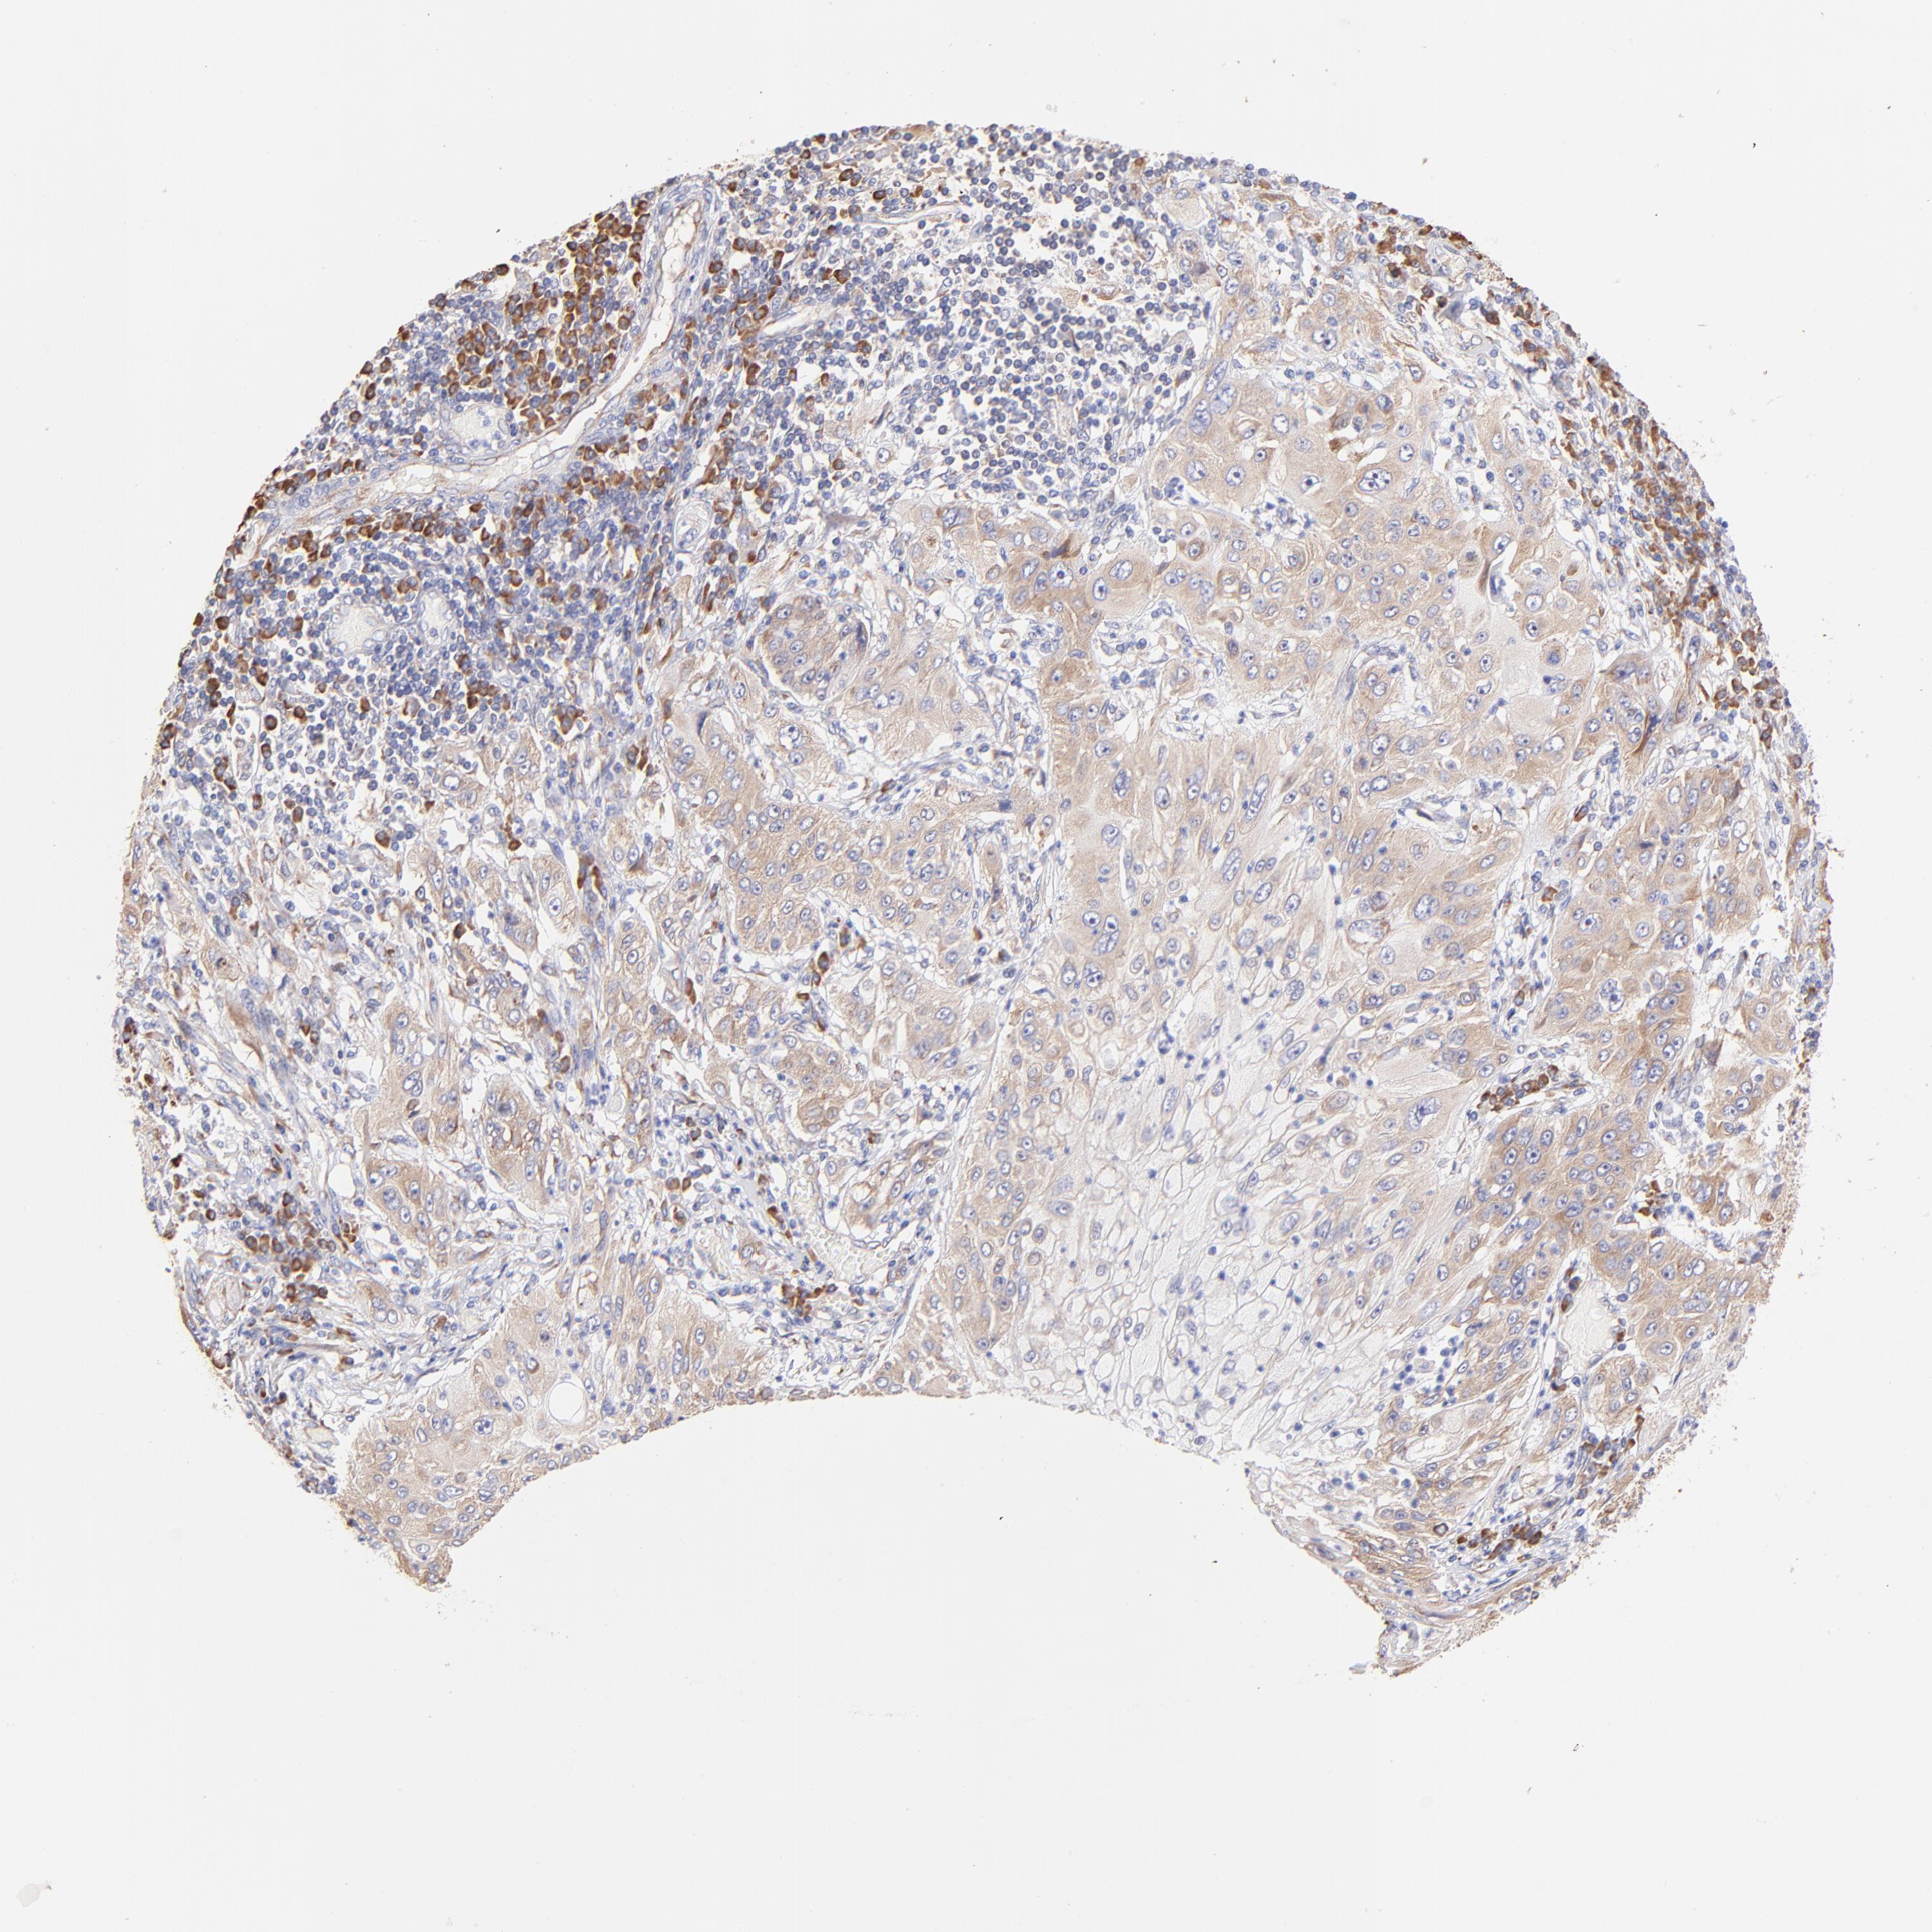

CANCER LUNG CANCER Show tissue menu

LUAD TCGA LUAD VALIDATION LUSC TCGA LUSC VALIDATION PROTEIN LUAD CPTAC PROTEIN LUSC CPTAC PROTEIN EXPRESSION